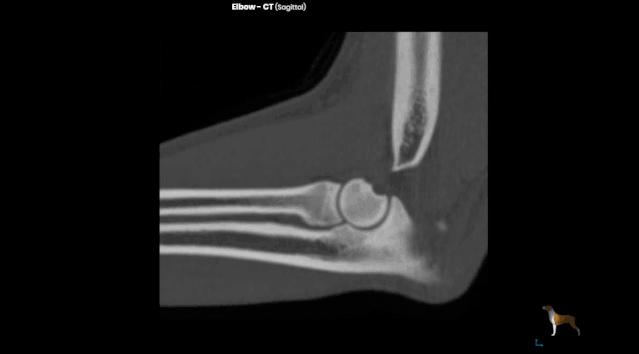

CT也是一种 X 线检查,它能对骨折部位进行多层的扫描,提供每一层的截面图像,使骨折的图像显现避免了其他组织的干扰,更清楚地显示出来。在普通的X线片上显示不出来骨折都能在CT片上清楚地显示。

术前x-ray显示,六一的骨折为 左前肢肱骨中远段骨折 ,骨折类型为横骨折。